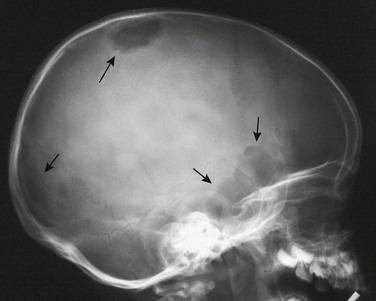

234. Taber, DS, Libshitz, HI, Cohen, MA. Treated Ewing sarcoma: radiographic appearance in response, recurrence, and new primaries. AJR Am J Roentgenol. 1983;140:753–758.